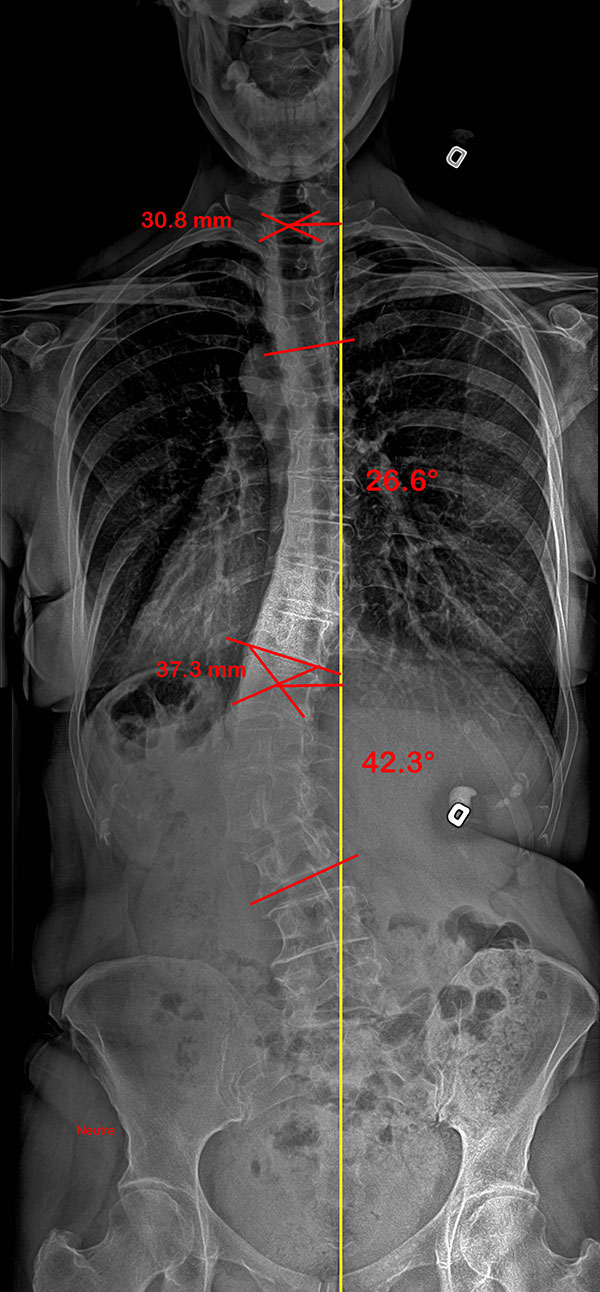

Colonne vertébrale d’une patiente scoliotique adulte, sans et avec SpineCor®

Colonne vertébrale avant SpineCor® |

Colonne vertébrale avec SpineCor® |

On remarque que, bien que la courbe n’ait pas changé de façon très significative, son alignement postural global est nettement amélioré par rapport à la ligne jaune centrale.